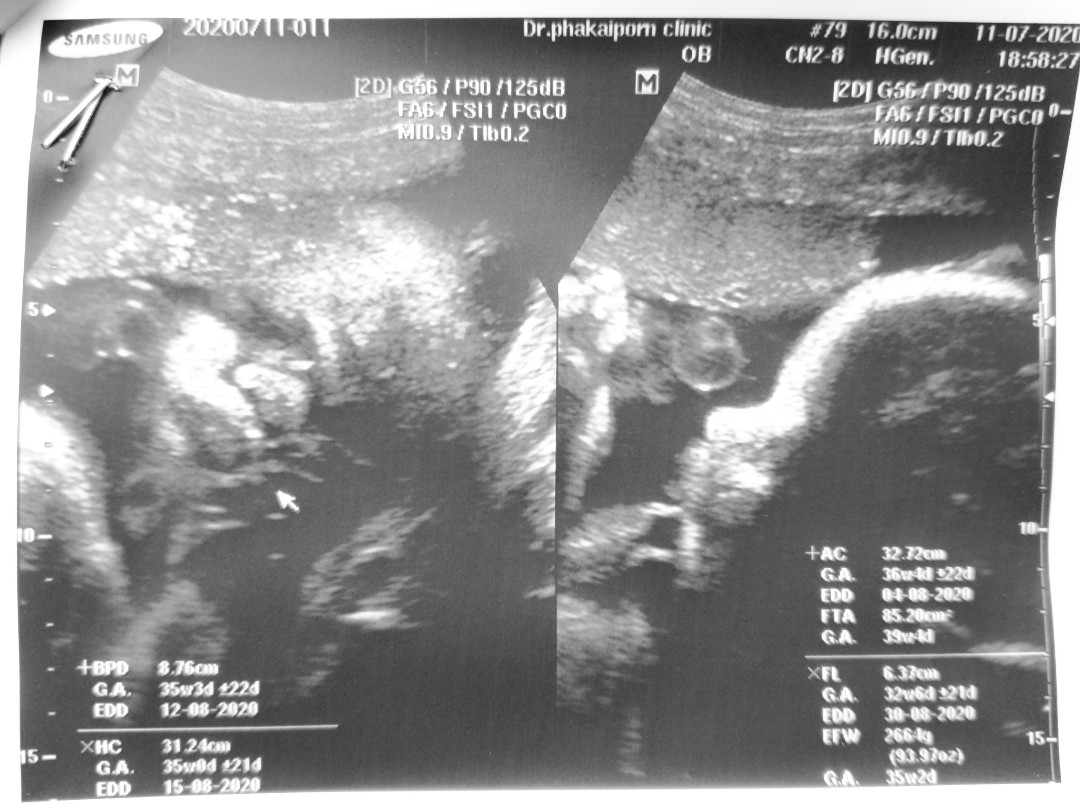

ภาพซาวน์ตอน30wค่ะ

30 W ผุ้ชายคัปป๋ม

28 สัปดาห์ ครับ